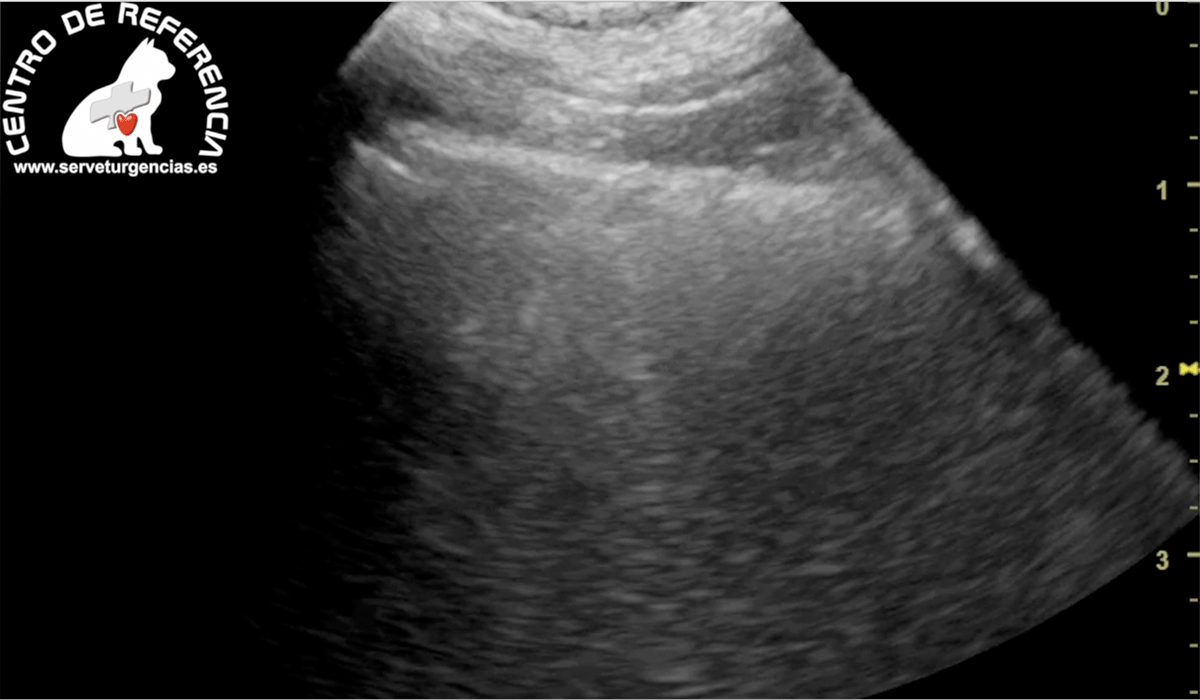

El edema pulmonar ocurre cuando se acumula líquido en los pulmonares, esto dificulta la respiración. La presencia de liquido en los pulmones interfiere con el intercambio de gases y puede causa insuficiencia respiratoria.

El edema pulmonar puede ser agudo (inicio repentino) o crónico (que ocurre más lentamente con el tiempo). Si es agudo, se clasifica como una emergencia y el animal a de ser atendido con celeridad.

La causa más común del edema pulmonar detectado en Servet urgencias veterinarias es la insuficiencia cardíaca congestiva, habitual en animales ancianos donde el corazón no puede cumplir con las demandas del cuerpo.